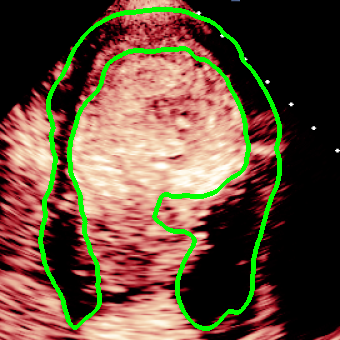

Visualization of myocardial segmentation from these methods is also shown in Fig. 4. We can see that for the Consensus, Confusion Matrix and Consistency methods, some unregulated shapes or discontinuity exist because the model cannot discriminate the actual myocardial from the artifacts which have the same intensity and texture information. However, the results of our method can alleviate the problem and accurately segment myocardium in MCE images.